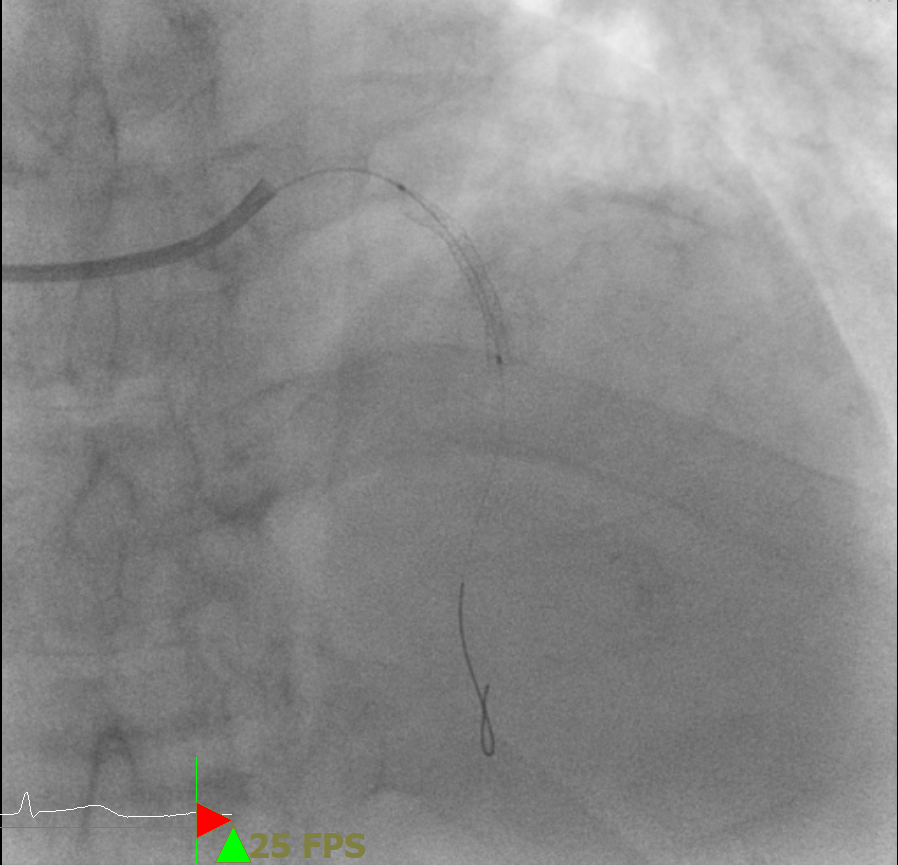

실제 관상동맥 조영술 중 촬영한 영상으로, 가늘고 기다란 카테터를 진입하여 심장의 관상동맥을 확인하고 좁아지거나 막힌 부분을 찾게 된다.